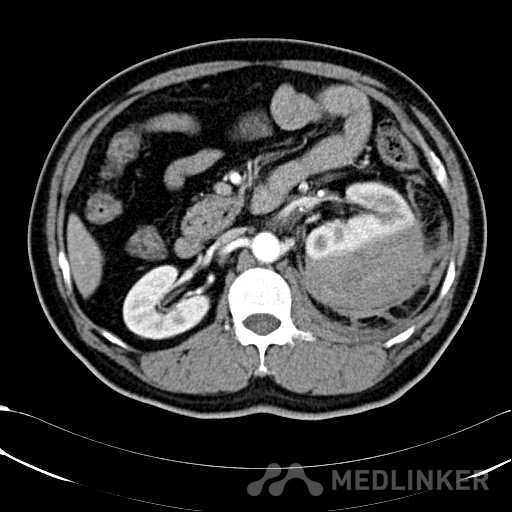

患者是54岁男性 主 诉: 突发左腰部疼痛3小时。 现病史: 缘于入院前3小时患者无明显诱因出现左腰部剧烈疼痛,无向他处放射,与活动及体位无明显关系,伴有腹胀、恶心、呕吐,无头痛、头晕,无人事不省、口吐白沫,无胸闷、胸痛、咯血,无发热、畏冷、寒战,大小便未解,肛门无停止排气,遂就诊我院,查“泌尿系彩超:左肾实质及不均质回声区,范围约9.4*4.1cm,界不清,内未见明显血流信号”,为进一步治疗,门诊拟“左肾占位”收住入院,发病以来,患者精神欠佳,未进食,大小便如前述,体重无明显改变。 患有“高血压病”7年,规则服药治疗(具体不详),监测血压情况不详。 T: 36.5 ℃ P: 65 次/分 R: 20 次/分 BP: 154/94 mmHg 双肾区皮肤无红肿、破溃及隆起,双肾肋下均不能被触及,左侧肾区叩击痛明显,右侧肾区无叩击痛,双侧肾区未闻及血管杂音。膀胱区无隆起,无压痛,耻骨上膀胱区叩诊空虚。外生殖器发育正常。 2016-04-12 泌尿系彩超:左肾实质及不均质回声区,范围约9.4*4.1cm,界不清,内未见明显血流信号。 04-12血常规:血红蛋白 151 g/L,白细胞 16.80 10^9/L,中性粒细胞百分比 84.90 %。急诊生化:白蛋白 39.8 g/L,葡萄糖 9.46 mmol/L。